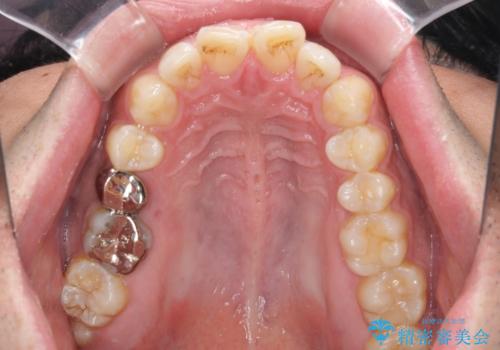

破折して抜歯が必要となった歯の後ろの歯は、根管治療が必要な状態であったので、根管治療を行い、矯正治療後にインプラント部の補綴治療と同時にセラミッククラウンを装着しました。

矯正治療以外に費用負担がかかることになりましたが、気になるところ全てを処置することができ、患者様には大変満足していただきました。